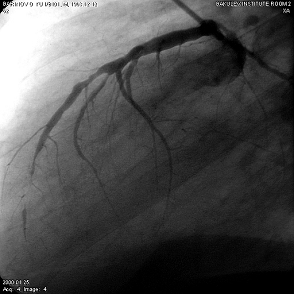

2.3.5 Коронароангиография (КГ), вентрикулография (ВГ)

Коронарографическое исследование проводили на ангиографических установках "Angioscope D" фирмы "Siemens" (Германия), "Integris 3000" фирмы "Philips" (Голландия) по методу М. Judkins и Sones. Для контрастирования КА использовали омнипак 300-350. КГ ЛКА выполняли в стандартных проекциях по методике Gensini: правая косая 150 и 450, левая косая проекция 600, левая боковая 900. В некоторых случаях использовали дополнительные проекции: левая передняя косая 450-750, каудокраниальная 300.КГ ПКА выполняли в стандартных проекциях: правой косой 450, левой косой 600, левой боковой 900 от сагиттальной оси. Анализ коронарограмм осуществляли на просмотровом аппарате "Tagarno 35AX". При анализе коронарограмм определяли тип кровоснабжения сердца, состояние основного ствола ЛКА, степень и уровень поражения коронарных артерий, диаметр коронарных артерий, количество пораженных артерий, наличие коллатерального кровотока.